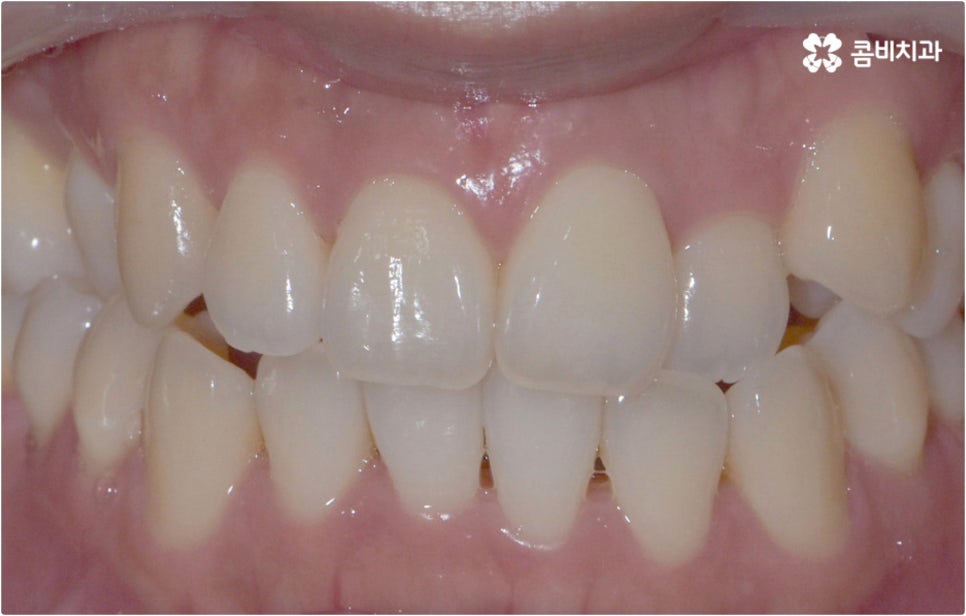

출처 아카이브 열기남녀노소 불문하고 많은 분들이 웃을 때 가지런하게 드러나는 희고 고른 치아에 대한 로망을 가지고 계실 거예요. 아무래도 환한 미소가 외모나 인상에 크게 영향을 주다보니 삐뚤빼뚤한 치아를 가지고 있거나 사이가 벌어지고 튀어나온 치아를 가진 경우 교정을 받아보고 싶다고 생각하시는 분들이 많으실 텐데요, 사실 업무상 또는 생활상 일이 많고 바쁘신 분들이나 대인 관계가 활발하여 겉으로 보이는 교정 장치가 부담스럽게 느껴지시는 분들은 치아 교정 치료를 진행하고 싶어도 평균적으로 1년 반에서 2년 반 정도 걸리는 기간이 마음에 걸려 고민하거나 지레 포기하실 수 있어요.

예를 들어 클리피씨교정 장치를 이용하면 기간적인 부분과 심미적인 부분의 부담을 함께 줄일 수 있어요. 예전처럼 미세 철사나 고무줄을 이용하여 와이어를 고정시키는 것이 아니라 자가결찰방식을 이용하기 때문에 클리피씨교정 장치를 사용하면 마찰로 손실되는 교정력이 줄어 보다 부드럽고 지속적인 치아 이동이 가능하게 되며, 치아 색상과 비슷한 세라믹 재질의 브라켓을 부착하기 때문에 말을 하거나 음식을 먹는 등 자연스럽게 입을 벌리는 상황에서 장치가 크게 눈에 띄지 않아 심미성 또한 우수하다고 할 수 있습니다. 이러한 장점으로 요즘 가장 많이 쓰이고 있는 장치는 역시 클리피씨 인데요, 이때 만약 환자분께서 아예 브라켓이 보이지 않는 것을 원한다고 한다면 치아설측교정 장치를 고려해 볼 수 있어요.

치아설측교정 은 겉으로 장치가 드러나지 않아서 가까운 사람이 아니면 교정 치료를 진행한다는 것을 알아차리기 힘들 정도로 심미성이 뛰어난데, 이러한 장점을 가지고 있는 반면 혀가 아랫니 쪽 장치에 닿다 보니 발음이 불분명해지거나 이물감 및 통증을 느끼는 경우가 있어 주의할 필요가 있어요.

이런 때는 치아설측교정 대신 비교적 잘 보이는 윗니는 설측으로 진행하고, 입술에 가려 잘 보이지 않는 아랫니는 순측(입술쪽)으로 진행하는 콤비교정을 이용하면 발음, 이물감, 통증 문제를 해결할 수 있습니다. 콤비교정 시 치아 겉면에 부착하는 아랫니 브라켓의 경우 치아와 색상이 비슷한 세라믹 재질을 이용하기 때문에 심미성도 크게 떨어지지 않으며 치아설측교정 으로 전체를 진행하는 것 보다 비용적인 부담도 줄여주므로 설측 교정 치료를 생각하시는 분들이라면 콤비교정 역시 함께 알아보시길 권유드리고 있어요.